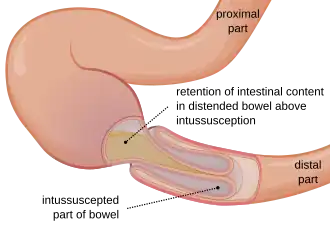

Intussusception is a medical condition in which a part of the intestine folds into the section immediately ahead of it.[1] It typically involves the small intestine and less commonly the large intestine.[1] Symptoms include abdominal pain which may come and go, vomiting, abdominal bloating, and bloody stool.[1] It often results in a small bowel obstruction.[1] Other complications may include peritonitis or bowel perforation.[1]

In the most frequent type of intussusception, the ileum enters the cecum. However, other types occur, such as when a part of the ileum or jejunum prolapses into itself.

The part that prolapses into the other is called the intussusceptum, and the part that receives it is called the intussuscipiens. Almost all intussusceptions occur with the intussusceptum having been located proximally to the intussuscipiens. This is because peristaltic action of the intestine pulls the proximal segment into the distal segment. There are, however, rare reports of the opposite being true.

An anatomic lead point (that is, a piece of intestinal tissue that protrudes into the bowel lumen) is present in approximately 10% of intussusceptions.[5] The lead point (best exemplified by a polyp) serves as a focal area of traction, which the peristaltic action pulls into the distal bowel, thus invaginating the attached bowel segment.[6]